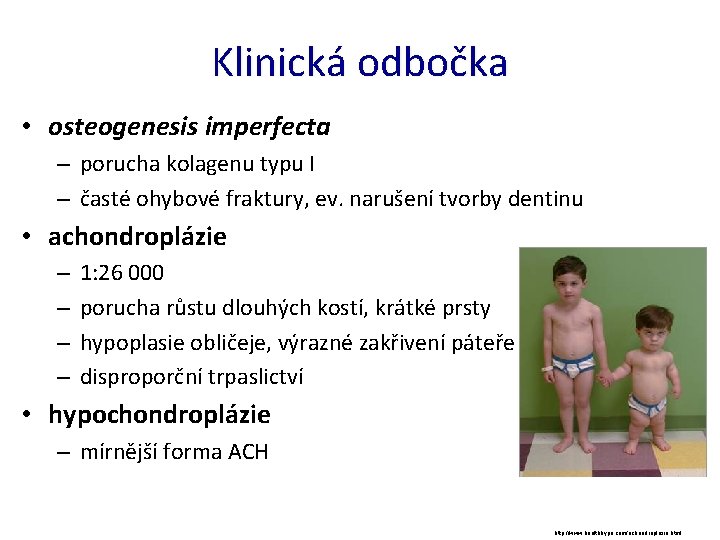

Klinická odbočka • osteogenesis imperfecta – porucha kolagenu typu I – časté ohybové fraktury, ev. narušení tvorby dentinu • achondroplázie – – 1: 26 000 porucha růstu dlouhých kostí, krátké prsty hypoplasie obličeje, výrazné zakřivení páteře disproporční trpaslictví • hypochondroplázie – mírnější forma ACH http: //www. healthhype. com/achondroplasia. html